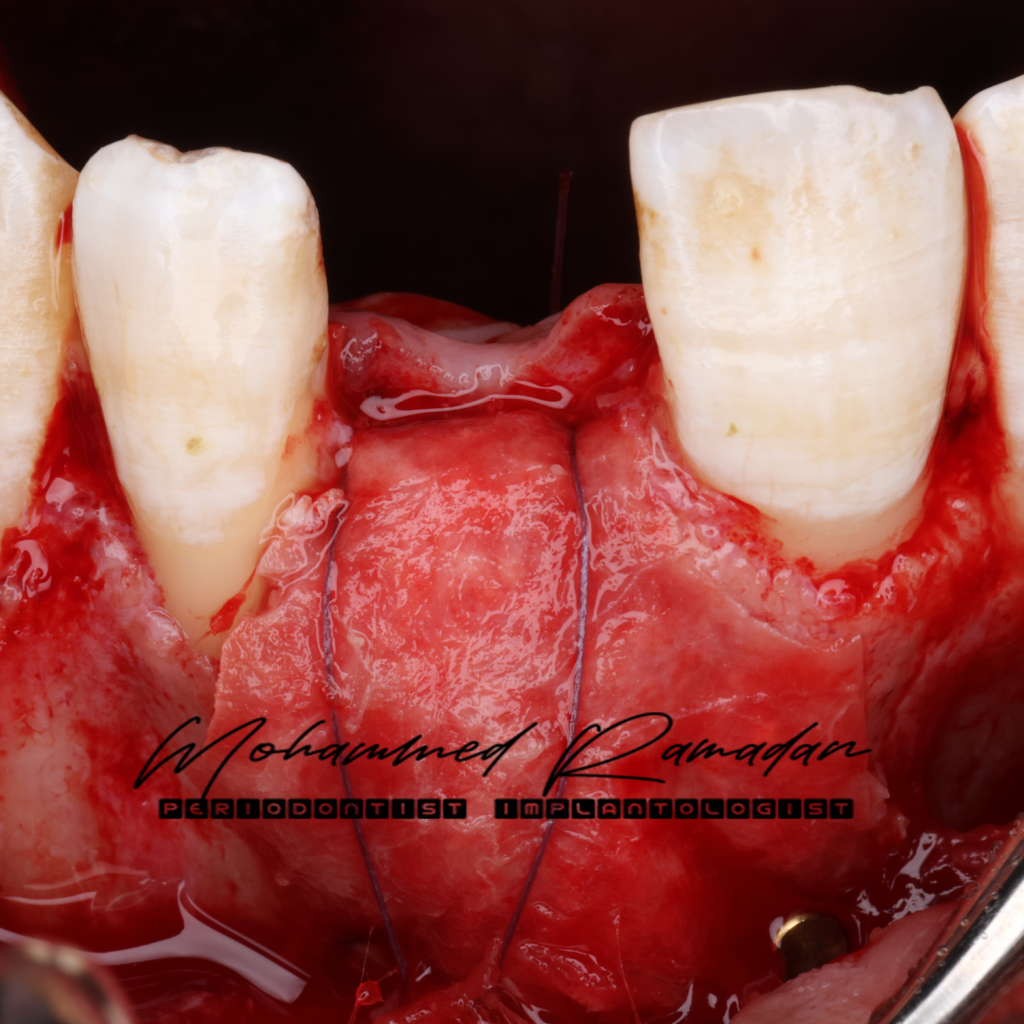

- Sub-epithelial connective tissue graft (CTG) placed via tunnel approach.